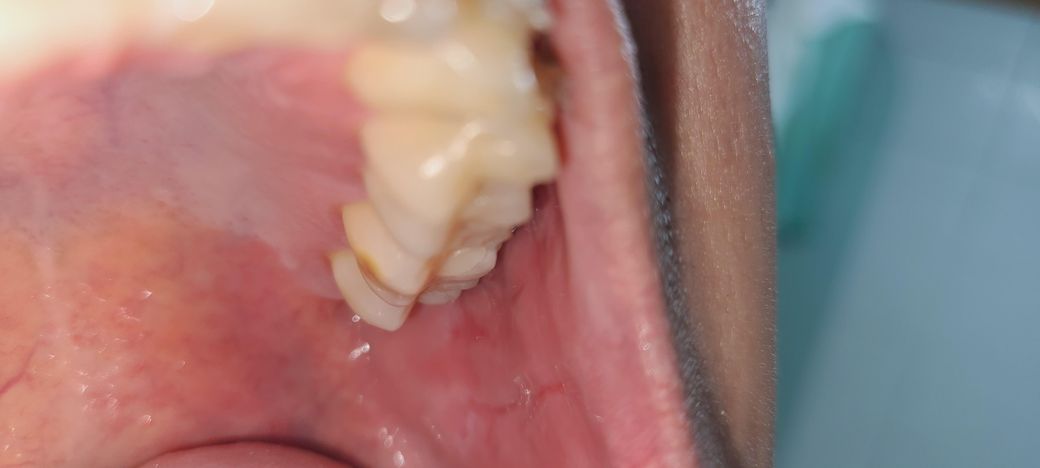

• 2번 째 사진

사진에 있는 부분이 충치로 보이진 않습니다. 크기가 더 커지거나 어두워지면 치과 가보시면 됩니다.

사진에 보이는 부분은 충치는 아니고 저부위만 치아 강화가 덜되서 저렇게 보이는겁니다. 큰 문제가 잇는건 아닙니다.

사진상으로 명확히 충치인지 여부가 확인이 되지 않습니다.갈색점이 있는 경우 충치의 가능성은 높으며, 초기에 확인ㅇ후 치료를 하는 것이 큰 치료를 막을수 있기에 치과에 방문하여 확인을 해보고, 필요시에 치료를 하길 권합니다.

사진으로는 정확한 확인이 어려워 보입니다.

충치가 아닐 가능성이 높어 보이지만.

정확한 확인을 위해서는 치과에서 진료를 받아보는것이 좋습니다.

충치의 가능성이 있고 진행이 빠르지는 않을 것 같습니다 또는 단순 치석침착일 수도 있습니다